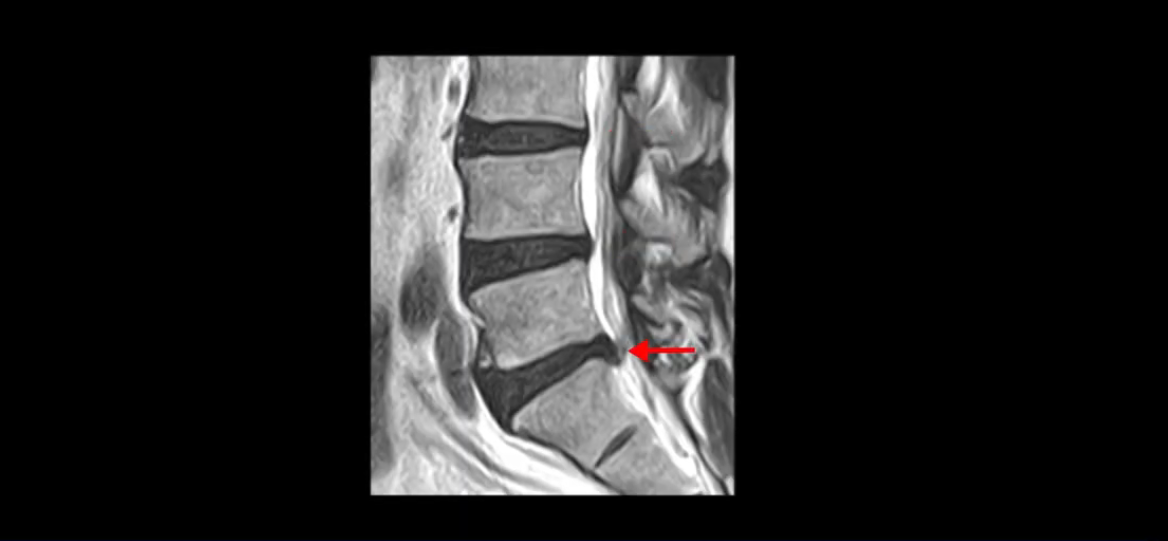

우선 이분 MRI를 잠깐 볼까요? 세 마디의 퇴행성 디스크가 있고

5번 1번이 파열되어 디스크 수핵이 밑으로 약간 흘러내려 있습니다.

단면을 보면 중앙 오른쪽으로 밀려 나왔는데 파열이 아주 심하지는 않습니다.

아주 심한 상태가 아니라서 방사통만 있지 마비, 즉 힘 빠짐은 없는 상태입니다. 이 정도의 크게 심하지 않은 디스크 탈출 정도라면 신경 주사 맞고 버티다 보면 좋아질 수도 있지만, 이 환자분은 보존한 지 10개월 후에 증상이 더 나빠집니다. 왜 그럴까요? 신경 주사도 전혀 듣질 않는데 어떻게 해야 수술 없이 좋아질 수 있을까요? 지금부터 설명해 드립니다.